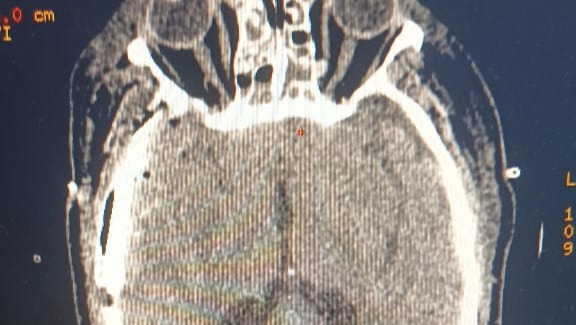

FRACTURA CRANEAL

En estos momentos se encuentra en la Clínica Colón de Ciudad Ojeda, estado Zulia, Venezuela, internado en la Unidad de Cuidados Intensivos (UCI), presenta múltiples fracturas como Craneal, torácica, y Clavícula, y con líquido en los pulmones.

Se han realizado varias tomografias, las cuales junto con la unidad de cuidados intensivos, asi como la cirugia craneal que le fue realizada, han sido uno de los mayores costos dentro del presupuesto generado por la clinica.